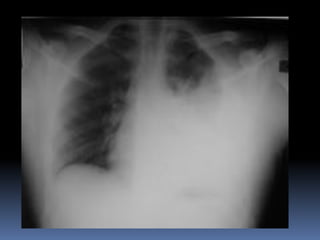

Abnormal Findings

Un equality of chest movement

Dullness on percussion

Decrease air entry

Tachypenic

heamothorax

chest tube